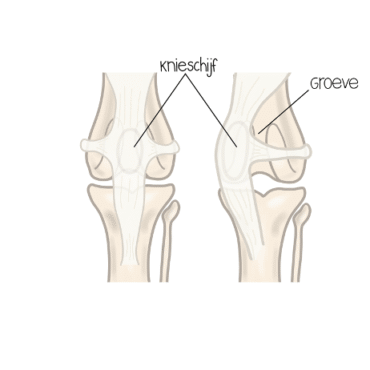

Patellaluxatie is een veelvoorkomende orthopedische aandoening bij honden. Hierbij schiet de knieschijf (patella) uit de groeve van het dijbeen, waar hij normaal in hoort te liggen. Dit kan naar de binnenkant (mediale luxatie) of de buitenkant (laterale luxatie) gebeuren. De aandoening ontstaat vaak door een afwijkende stand van de achterpoot of door een te ondiepe groeve in het dijbeen. Patellaluxatie komt regelmatig voor bij kleine hondenrassen, maar kan ook bij middelgrote en grote rassen optreden. In de meeste gevallen is de luxatie naar binnen (mediale luxatie).

- Verdiepen van de groeve: de “gleuf” in het dijbeen waarin de knieschijf hoort te lopen, wordt iets dieper gemaakt. Zo blijft de knieschijf beter op zijn plek.